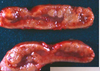

Mdx?

Entropion and secondary trichiasis